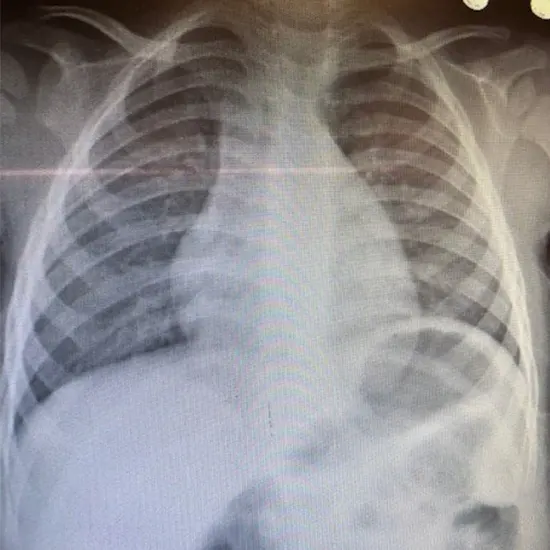

X Ray Chest 450 225